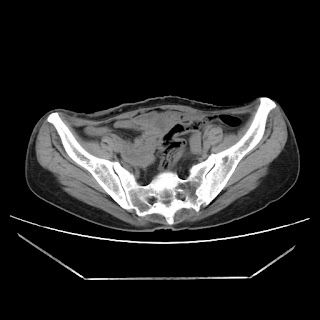

Radiological images:

CT-Scan investigation done on 16Apr16